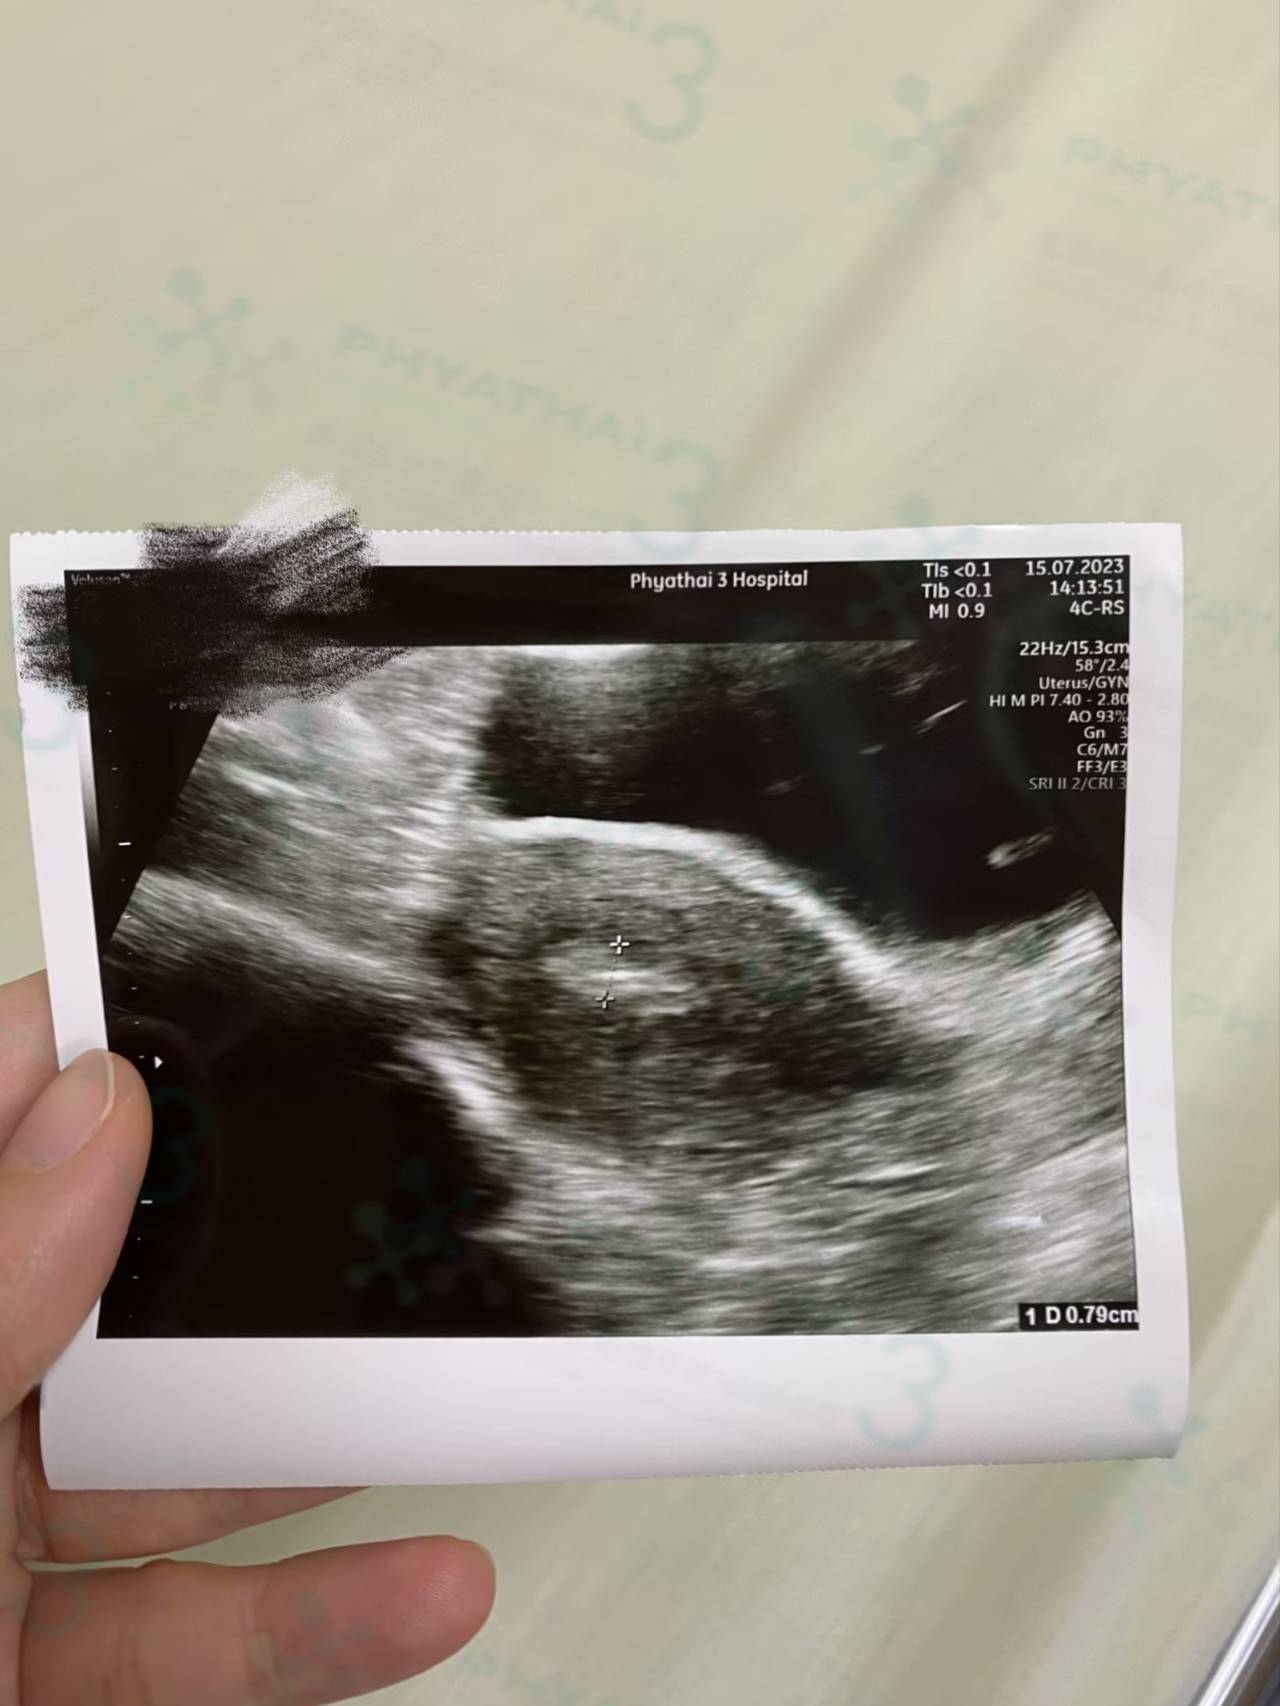

终于到了最后一步,今天高年龄来移植的患者 , 女士39岁一次成功有3枚胚胎能移植 。对于高年龄的人来说算是很好的结果了 ,因为染色体异常率根据女士的年龄有关。现在已经39岁了但有胚胎移植实验室超级棒。 非常感谢帕雅泰3医院,一次心想事成有宝贝能移植。在等移植中女士说同一批来的患者,现在很多患者已怀孕成功。我也希望自己也好孕一次成功。 今天移植的流程好顺利,移植的部位也超级好在子宫中间。 我们移植后生活翻译还对患者很贴心每天安排送早餐给患者。 这服务对一个人过来移植的患者就很方,先生也能安心。我们希望这段时间胚胎着床顺利。